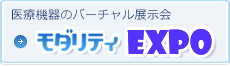

ドックや日常検査で心臓CTやSEMARを活用

心臓CTは診療とドックを合わせて月間2、3件。精査目的の検査では、βブロッカーを使用して心拍数をコントロールした撮影を心掛けている。Aquilion Lightning/Helios Editionは、ガントリ回転速度が最速0.5秒だが、“PhaseNAVI”で静止位相を取得することで冠動脈のプラークと石灰化の評価が可能になっている(図1)。齋藤名誉院長は、「心臓CTの件数は、まだ多くはありませんが、病変の有無や治療方針の決定について確実に判断ができる画像が得られています。件数についても、今後少しずつ増やしていく予定です」と述べる。

■Aquilion Lightning/Helios Editionによる臨床画像

図1 狭心症の心臓CT

a:VR画像 b:LAD c:LCX 冠動脈プラークや石灰化を高精度に描出可能